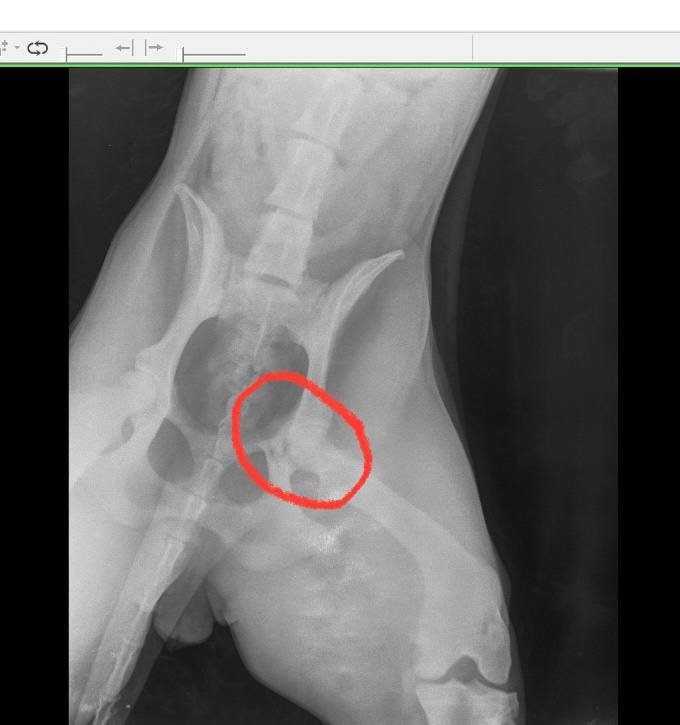

Это было утром примерно в 7:50 утра, я повез в ближайшую клинику (кое-как дотащил её до машины на руках, она весит 35 кг примерно, а у меня еще вторая собака была со мной, хорошо какая-то женщина увидела, помогла вторую довести до машины), но клиника оказалось закрытой, повёз в другое место. Там сделали снимки, оказалось, что удар пришелся в заднюю часть (как позже выяснилось - это был перелом вертлужной впадины).

Я посетил 4 разные клиники, отправлял снимки в Новосибирск, батя смотрел (он хирург) и своему другу отправил в Питер, он там тоже какой-то врач травматолог вроде хороший. И, сука, все говорят по-разному. Начиная с банального обезбола, заканчивая заключениями. В одной клинике вообще говорили, что это не перелом (по снимкам).

3 человеческих врача сказали, что нужно оперировать, в Новосибирской клинике (самой лучшей типа там в России или Новосибирске, хуй пойми, называется "Бэст", там типа топовый травматолог) тоже сказали, что надо делать операцию. А другие (из первой клиники врач и из той, где я в конечном итоге делал остальные снимки, сказали, что операция не требуется). Короче говоря, я вообще запутался, везде всё по-разному назначали, разные таблетки и т.д. Операция в районе 70 косарей стоила, последний врач (вроде тоже какой-то при наградах, на какие-то там съезды ездил как раз по моему вопросу, по эндопротезированию и  т.д.) сказал, что не надо операцию делать первую (когда штифт ставят в кость, чтобы срослось ровно), а сказал, что так зарастёт, а в случае чего можно потом удалить головку бедра. В общем я дней десять собаку на руках выносил из дома, она вообще не вставала и просто лежала, мучалась, скулила, я ей обезбол по кд колол, даже в туалет не могла сходить (неделю не срала и три дня не ссала). В клиники на руках таскал, сам измучался весь. Опыт, который не хочется переживать еще раз.

Снимки в декабре и в феврале.

Вот снизу уже срослось, но видно, что кривовато немного.